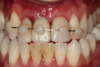

The next case follows the digital protocol for fully guided surgery and prosthetics. A CBCT radiograph, digital impression, and digital photography were the cornerstones to the success of this case. The 3D data set was electronically delivered to the dental laboratory. The data were merged and the process to develop the plan was initiated. The use of CBCT was essential in this case, particularly due to minimal space for placement of individual implants and single-unit crowns. The patient's chief concern was that she wanted to have single-unit crowns instead of fixed crown-and-bridge restorations because she was worried that she would someday find herself in an assisted-living facility; if that were to happen, she wondered, who would help floss under her bridge work? Her decision was to have single implants with individual crowns. CBCT technology is much more accurate in evaluating space maintenance and management.10 Periapicals in the past were rather close for calculating spacing; however, the CBCT identifies the buccal-lingual dimensions as well as the mesial-distal measurements. On review of the completed proposals for implant placement and provisionals, it was determined that there was sufficient spacing for implant placement to allow appropriate emergence profiles for the provisionals and then eventually the final single-unit cemented crowns. The proposal was accepted, and a 3D-printed surgical stent was fabricated, along with the PMMA provisionals (Figure 29 through Figure 35).

On the day of surgery, the plan was to extract teeth Nos. 21, 23, 24, 25, and 26, place 3.0 x 13-mm implants in the anterior region due to limited spacing, and place a 4.1 x 10-mm implant in the No. 21 extraction site. Before the extractions were performed, the No. 23 pontic was sectioned from the existing 2-unit cantilevered bridge utilizing ceramic and metal high speed rotary cutting burs ZR 6881 and H34L (Komet-USA), respectively. After removal of the pontic and extractions, the surgical guide was verified to be seating positively (Figure 36 through Figure 38). Surgical guide protocol was followed, and all implants were successfully placed and torqued to a value of greater than 35 Ncm (Figure 39 and Figure 40). All implants were placed without flapping, with the exception of No. 23. The flap was elevated to reposition lingual keratinized tissue facially for enhanced esthetic tissue profile. The implants were then prepared with a high-speed carbide bur (Komet-USA) with copious amounts of water (Figure 41 and Figure 42). The one-piece 3.0-mm diameter implant served the needs of the patient's spacing requirements. Inter-occlusal space requirements and path of draw were verified. The PMMA provisionals were air abraded and relined with crown-and-bridge material (Figure 43 through Figure 45).

Due to the guided surgical and prosthetic protocol, this case was completed with tissue sparing and atraumatic extractions with precision implant placement. The most arduous task of the entire procedure was the physical implant abutment preparation for proper clearance. If the patient had more space to plan her treatment, implants using a two-piece protocol would have been implemented with screw-retained non-engaging provisionals after implant placement. Again, this decision process is solely in the hands of the clinician providing services.

Digital workflow for this case was straightforward. The patient was pleasantly surprised with the results. She mentioned that she can now rest easily at night, even if she finds herself in an assisted-care facility.

Fig 36. Anterior central view.

Figure 36